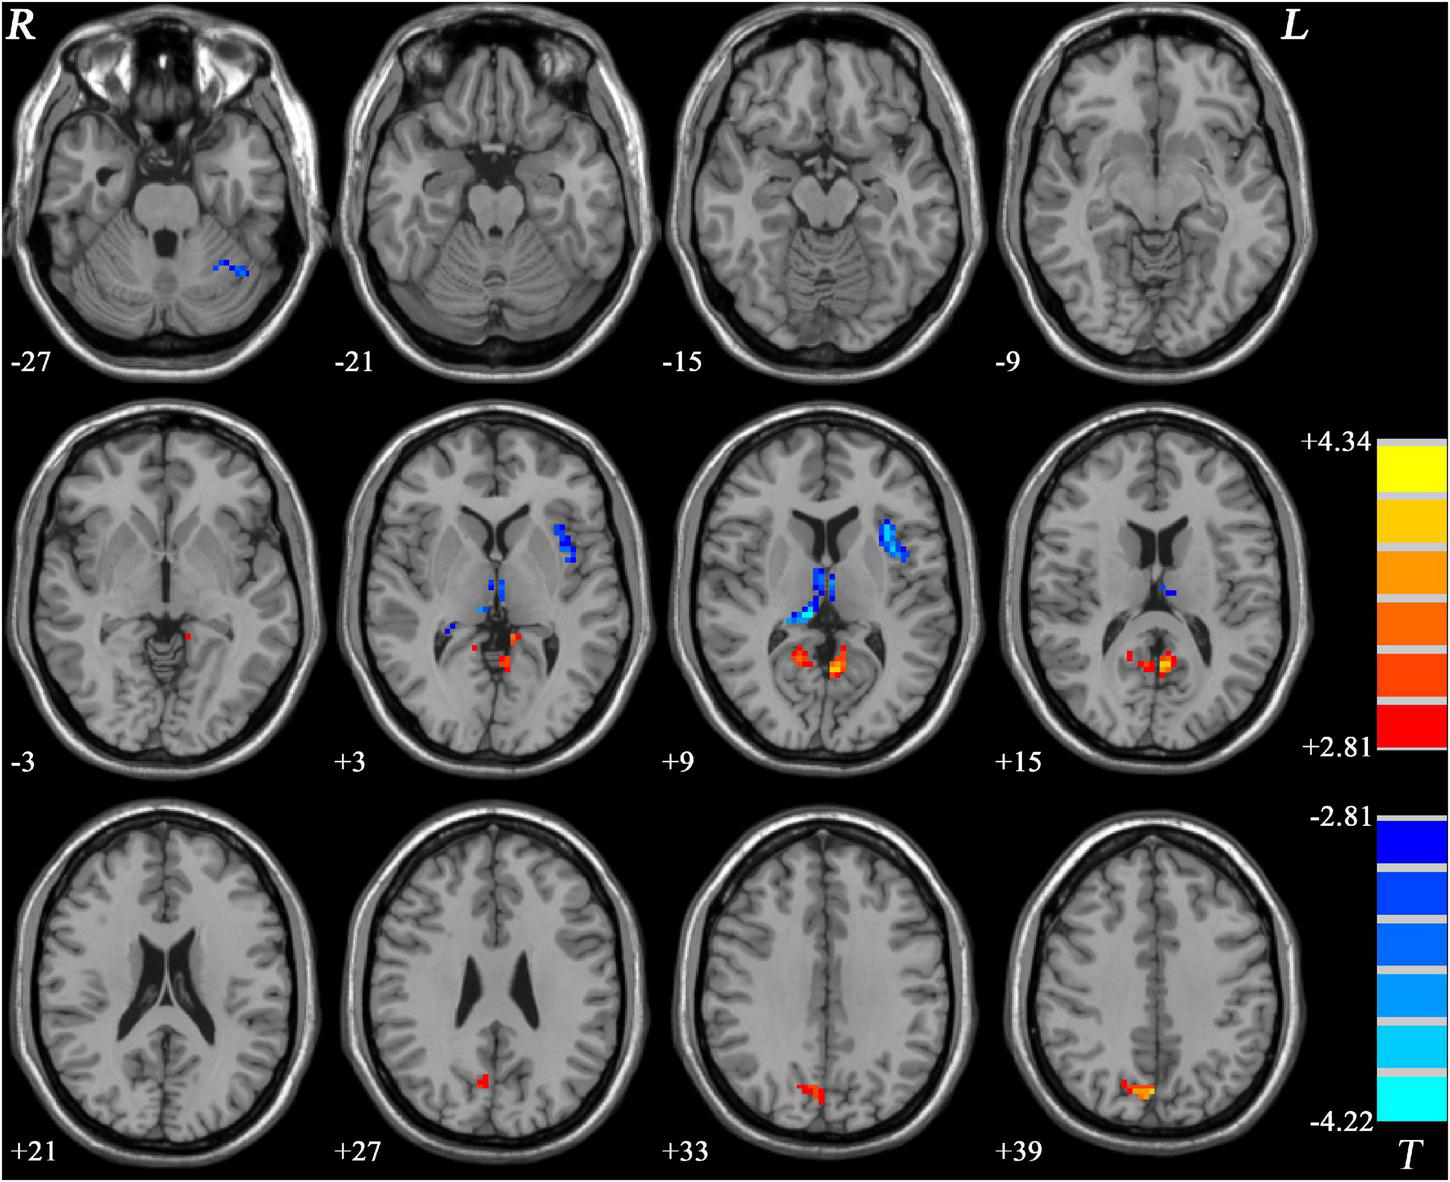

GI-MDD patients, relative to nGI-MDD patients, exhibited increased PAS scores in the left inferior frontal gyrus (IFG) and left superior medial prefrontal cortex (MPFC). Moreover, a reduction in PAS was observed in GI-MDD patients in the right postcentral gyrus of the somatomotor network (Table 2 and Figure 2).

Figure 2. Regions with significantly different PAS scores in comparison between GI-MDD and nGI-MDD patients without GI symptoms. The color bar indicates the T-values from post hoc t-tests. GI-MDD, major depressive disorder with gastrointestinal symptoms; nGI-MDD, major depressive disorder without gastrointestinal symptoms; PAS, parameter of asymmetry.

This study investigated the effect of GI symptoms on functional asymmetry in first-episode, treatment-naive MDD patients. In comparison across three groups, we found that the regions with significant differences were dominantly distributed in the left hemisphere and involved multiple brain networks including the DMN, visual network, frontoparietal network, and cerebellum. Increased PAS scores in the left IFG and left superior MPFC and decreased PAS scores in the right postcentral gyrus were found in comparison between GI-MDD and nGI-MDD patients. The PAS scores of the left IFG and left superior MPFC were correlated with the severity of GI problems and, more importantly, they could better meet the requirment of discrimination between GI-MDD and nGI-MDD patients. In addition, increased PAS scores in the PCC/precuneus were found in both GI-MDD and nGI-MDD patients.